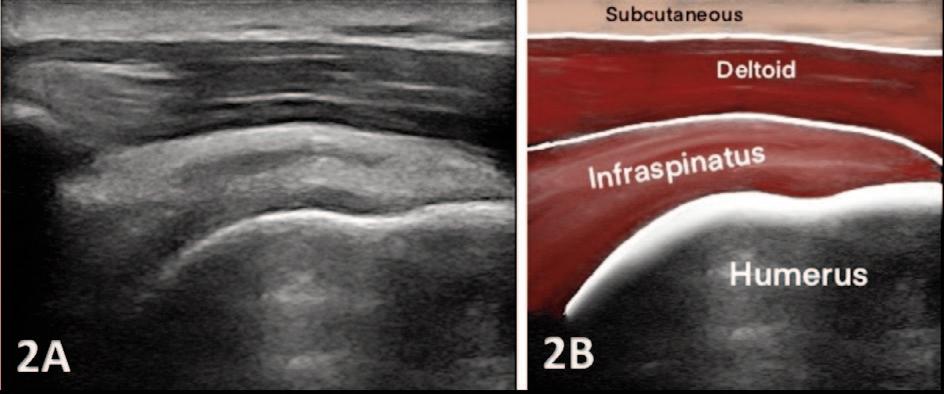

935 Utilizing Diagnostic Musculoskeletal Ultrasound for Assessment of the Infraspinatus Muscle and Tendon: Implications for Rehabilitation Professionals. Manske RC, Voight M, Wolfe C, Page P.